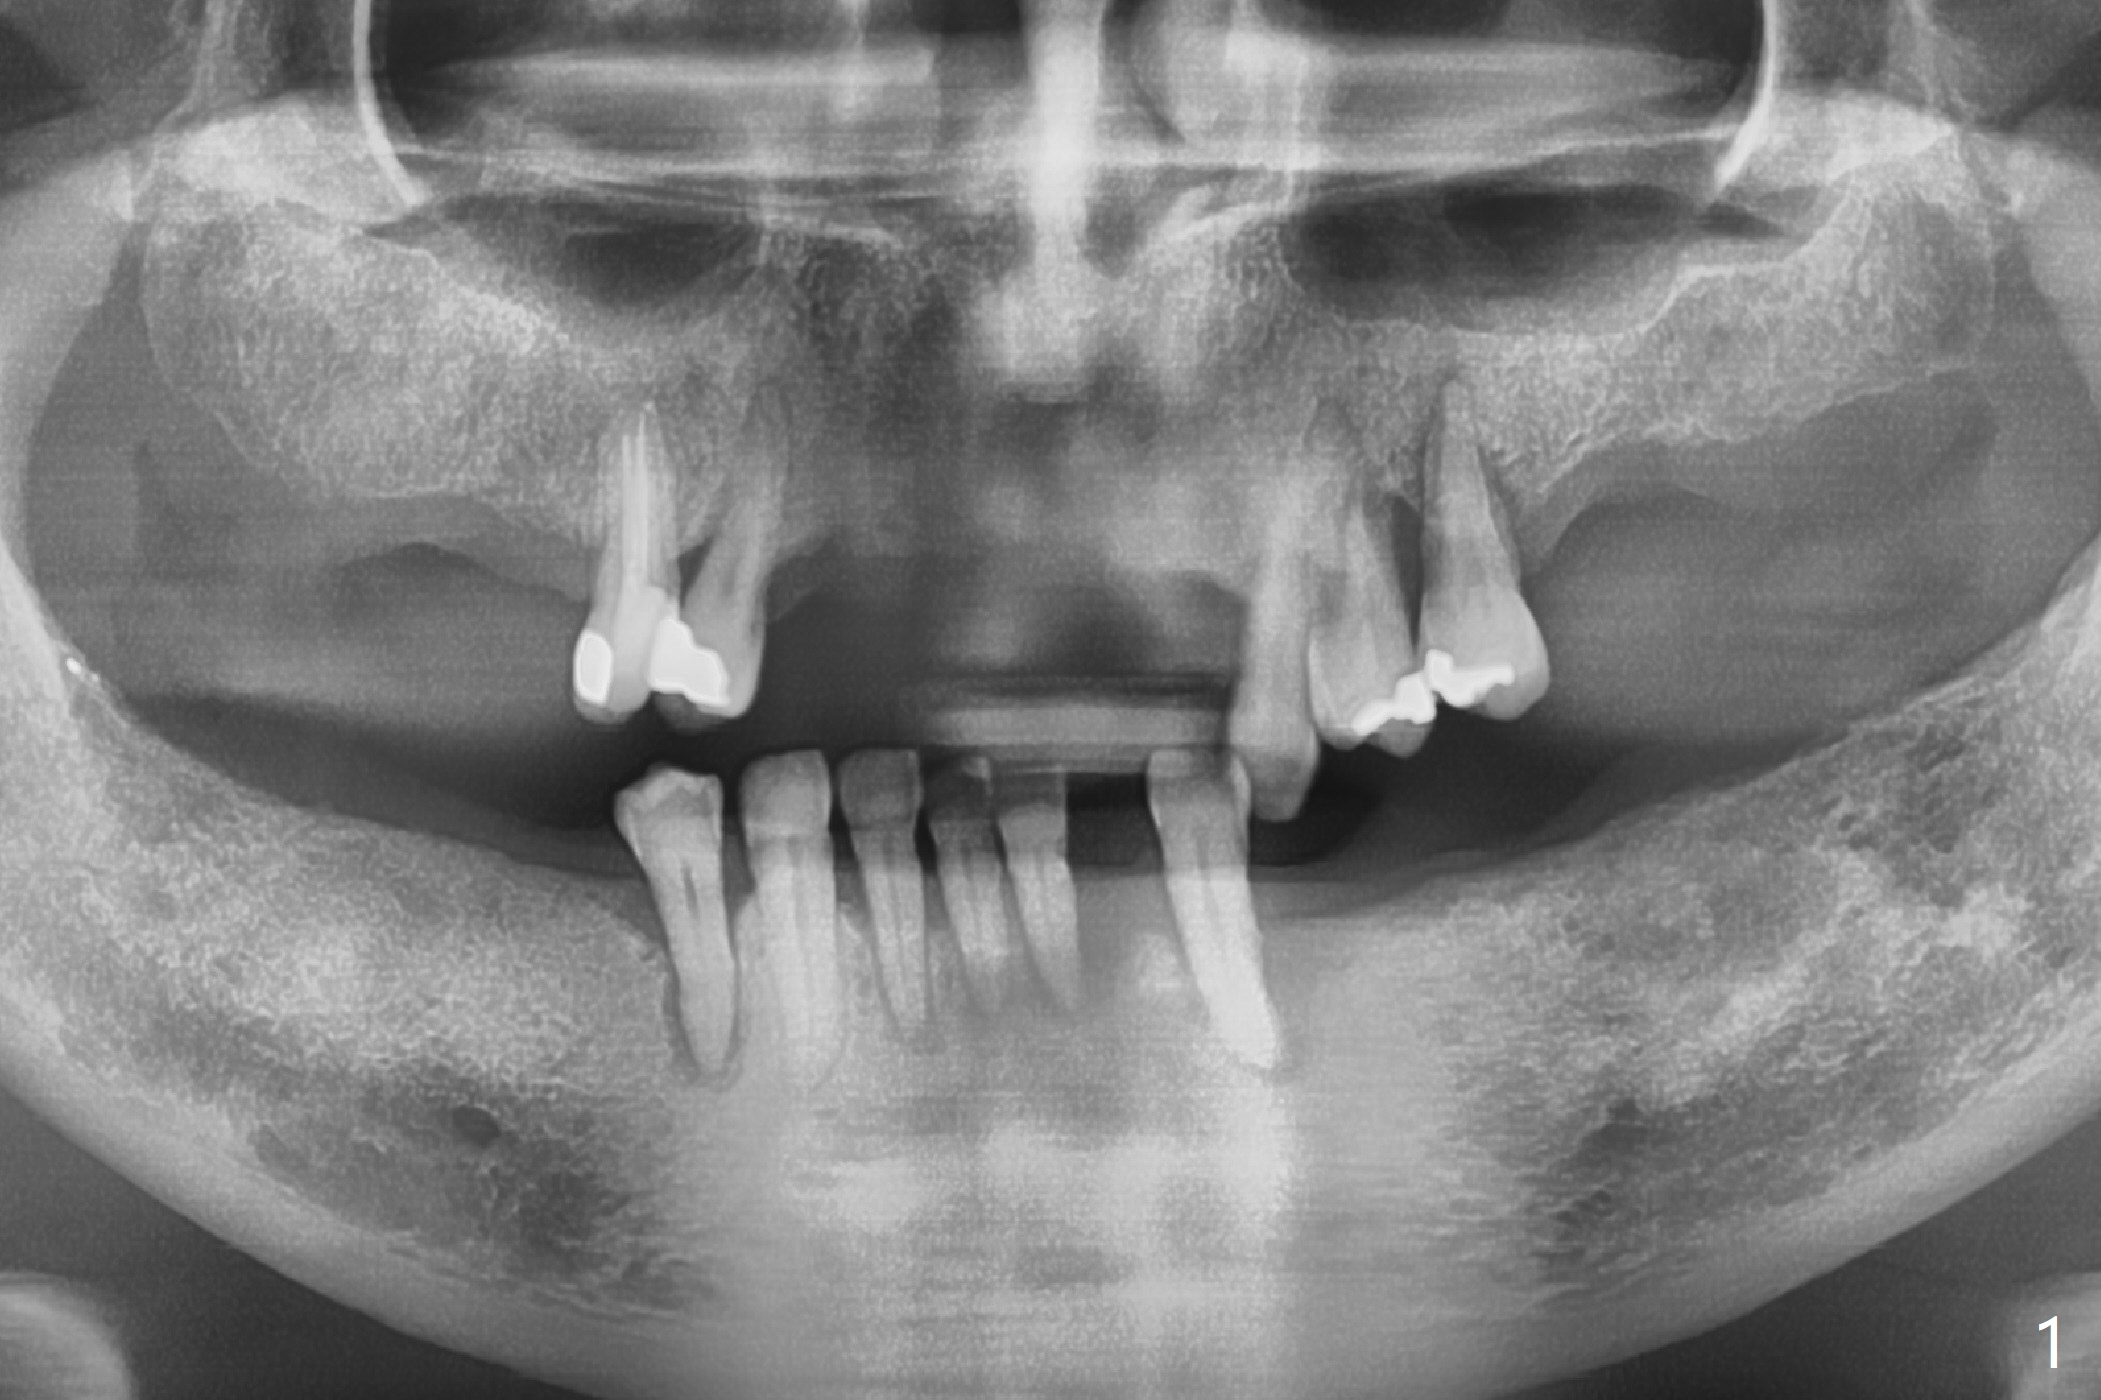

A 50-year-old woman (dentophobic, smoker, 1/3 pack per day) has chronic periodontitis with terminal dentition (Fig.1). Provisional RPDs are 5 years old. Before fabricating permanent RPDs, nonsalvageable teeth, for example #22, should be extracted and replaced with an implant with ball abutment (Fig.2). Because of fear and finance, one implant will be placed each time.